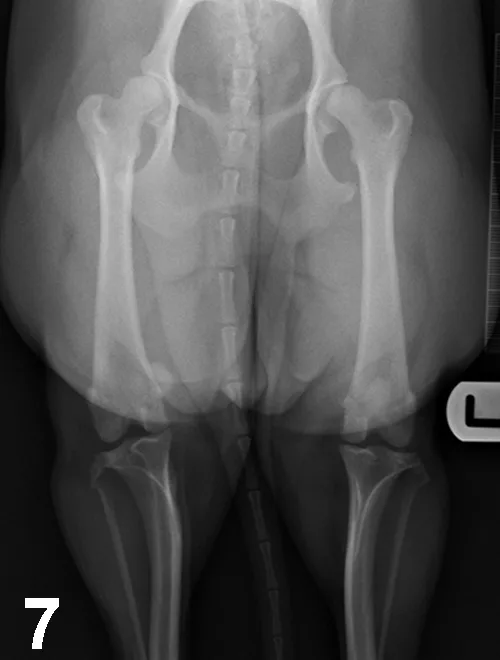

Mediolateral radiographs of the shoulder in an 8-month-old German short-haired pointer with left forelimb lameness. Flattening of the humeral head with sclerosis of the underlying subchondral bone suggests OCD.

Large-breed dogs are most commonly affected, usually presenting with unilateral or bilateral forelimb lameness between 4 and 8 months of age. Muscle atrophy and pain during shoulder manipulation may be found in affected dogs. Diagnosis is based on clinical signs and radiographic visualization of flattening of the caudal aspect of the humeral head (Figure 10A). Positive-contrast arthrography may help in the diagnosis when radiographs are unclear (Figure 10B). Advanced imaging (eg, CT, MRI) can be helpful in elusive cases.Surgical or arthroscopic removal of the cartilage flap with debridement of the subchondral bone often leads to an excellent prognosis (Figure 10C).